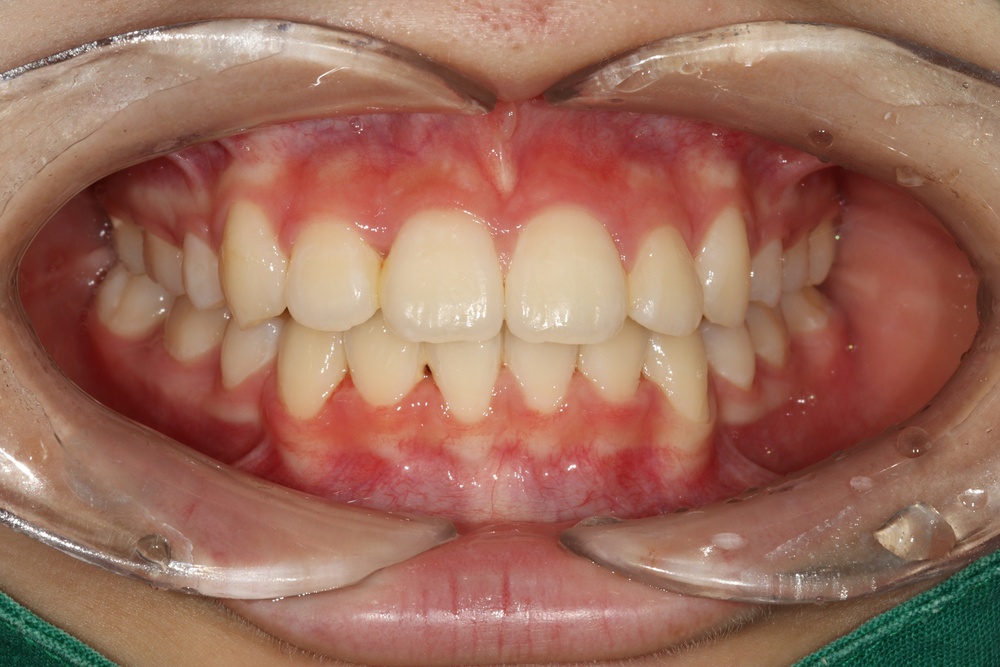

치아가 가지런해졌고, 윗니 치아 사이의 틈도 메꿔졌으며, 치아에 있던 충치도 모두 치료하였습니다.